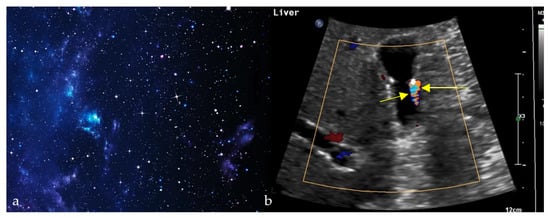

Cosmic Signs in Radiology: A Pictorial Review

Pattern recognition remains a cornerstone of radiologic interpretation, as it facilitates a confident and comprehensive differential diagnosis. Certain pathologies present with specific and highly recognizable patterns on imaging modalities. These patterns can resemble familiar real-life phenomena, including cosmic bodies that surround us. We present in this article a compilation of radiologic signs across various modalities that take inspiration from cosmic phenomena. For each sign, we summarize its defining imaging appearance, typical clinical context, and common pitfalls; where available, we note diagnostic performance (e.g., sensitivity/specificity) to guide appropriate weighting in practice. By coupling memorable imagery with succinct clinical guidance, this pictorial review aims to support a faster, more accurate pattern recognition that is applicable in both low-resource and tertiary care settings, while recognizing that these signs function as educational aids rather than validated diagnostic tests. In familiarizing themselves with these classic signs, training radiologists can benefit from an engaging and memorable way of recognizing various pathological conditions. Full article

Figure 1